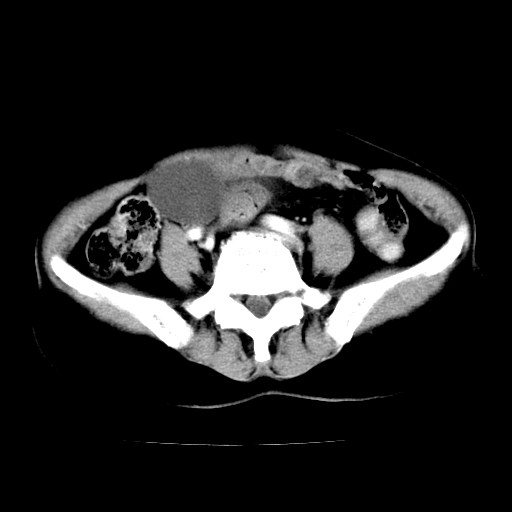

标题: CT24785:女,62岁,发现下腹部肿物半年。

女,62岁,发现下腹部肿物半年,下腹部不适。

该年龄性别首先考虑平滑肌肉瘤可能性大,其他待排除。

考虑子宫平滑肌肉瘤可能性大。

卵巢囊腺瘤或囊腺癌,建议免疫组化实验